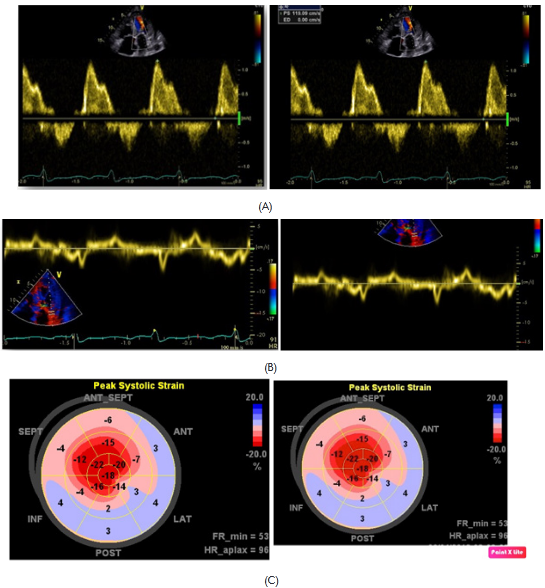

Figure 2 diastolic mitral flows with pseudo normal pattern (A). E´ wave plainly decreased to the side mitral ring level (B). Global longitudinal strain with normal values at apical level and diminished in mid and basal segments (C).

Subsequently, she was admitted to our institution with a clinic diagnosis of acute heart failure, Stevenson B. A chest X-ray showed bilateral pleural effusion, grade II. During the admission, the only significant finding was mild anemia (Hb 11,1g/dl). A transthoracic echocardiogram (Figure 1 & Video 1) was done showing normal left ventricle diameters, LV ejection fraction 47%, mild concentric hypertrophy, biatrial enlargement, mild to moderate mitral regurgitation, pseudo normal ventricular filling pattern, e 4cm/sec, E/e´ ratio greater than 18, moderate tricuspid insufficiency, an estimate pulmonary artery systolic pressure of 55mmHg and mild pericardial effusion. The presumptive diagnosis of infiltrative restrictive cardiomyopathy was assumed. A myocardial 3D strain imaging with speckle tracking was done, showing normal longitudinal strain of apical segments and a strong impaired values of basal and mid segments (-16 to -28 at apical segments vs 4 to -4 at basal level) (Figure 2C). The patient improved clinically with diuretics and vasodilators according to local guidelines. Nevertheless, during the third day of hospitalization she experiences a sudden death episode, with ventricular tachycardia documented in the telemetric system, with an adequate response to cardiopulmonary resuscitation (CPR).

Imaging studies are clearly useful; nevertheless, they do not show specific data to differentiate the diverse types of diseases. Classic data include normal size ventricles with mild hypertrophy, biatrial enlargement, changes in the ventricular filling pattern (pseudo normal or restrictive pattern) and pericardial effusion. The myocardial assessment with longitudinal strain shows a very important characteristic pattern for the diagnosis, characterized by strain values diminished to basal level and mid segments, with normal values of apical segments. These findings may be present in absence of ventricular motility disorders, so the benefit is understandable8 Our patient presented all these features.